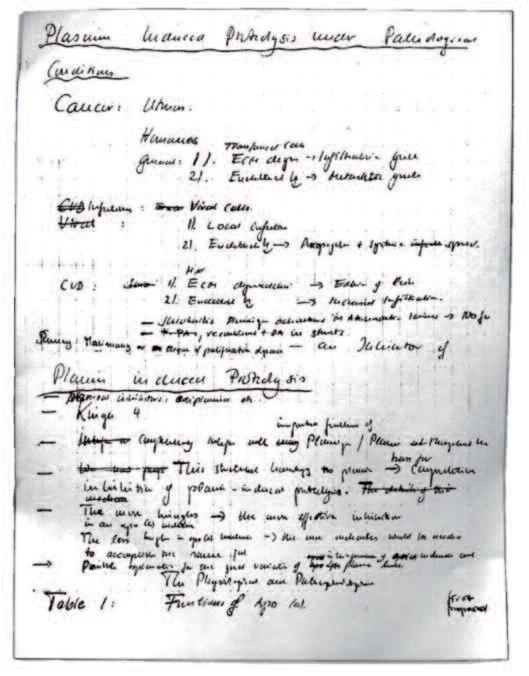

Le scoperte riportate nel seguente capitolo sono state fatte più di due decenni fa. La pagina a fianco mostra una pagina del mio manoscritto, pubblicato all'inizio del 1992 con il titolo "Proteolisi indotta da plasmina". Descrive per la prima volta che il meccanismo chiave della diffusione del cancro, la digestione del collagene, può essere bloccato da sostanze naturali. Il premio Nobel Linus Pauling ha sostenuto la vasta portata delle conclusioni di questa pubblicazione: l'attuazione di queste scoperte nella medicina porterà al controllo naturale del cancro. Immediatamente dopo questa pubblicazione, la digestione del collagene ha assunto un ruolo centrale in molte conferenze scientifiche. Ha inoltre innescato una corsa tra le aziende farmaceutiche per poter trovare delle molecole di origine sintetica, capaci di bloccare questo meccanismo, che le industrie potevano brevettare. Dieci anni dopo, il 12 maggio 2002, il San Francisco Chronicle ha pubblicato un articolo su questa intensa gara intitolato Misdiagnosis (Errori di diagnosi). Senza fare riferimento al rapporto originale sugli esiti di questi studi, riportava la gara tra le aziende farmaceutiche per trovare quello che il giornale chiamava il ‘Santo Graal della medicina’, la soluzione per la battaglia contro il cancro.

Plasmin-Induced Proteolysis and the Role of Apoprotein(a), Lysine, and Synthetic Lysine Analogs

Matthias Rath e Linus Pauling Journal of Orthomolecular Medicine, 1992, 7, 17-22

il testo integrale è contenuto in appendice